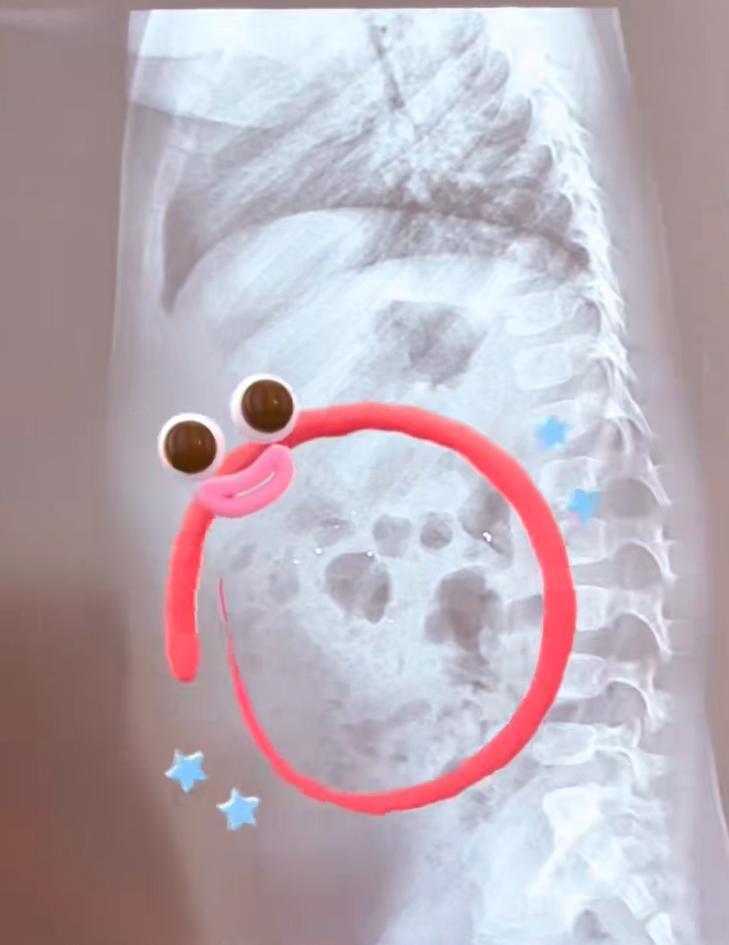

處理完現場,媽媽立刻帶着佑佑趕往醫院。醫生給孩子拍了片子,結果顯示腸道里確實有一些亮晶晶的散落陰影——正是那些水銀珠。幸好,孩子的腸道也沒有破損。

片子裏的亮晶晶的東西就是水銀珠,回去後讓孩子多喫多喝,特別是富含膳食纖維的食物,比如火龍果、西梅、韭菜、黑木耳等,促進腸道蠕動,水銀就能隨着糞便排出來。

於是,媽媽按照醫囑,給孩子準備了韭菜餃子、青菜,又買了火龍果和西梅,讓孩子可勁兒地喫。等到第二天下午,孩子上過廁所後,媽媽又帶他去醫院拍片複查。醫生一看新片子,裏面已經基本沒有亮晶晶的陰影了,對媽媽豎起了大拇指:“處理得非常正確,執行得也很好!”